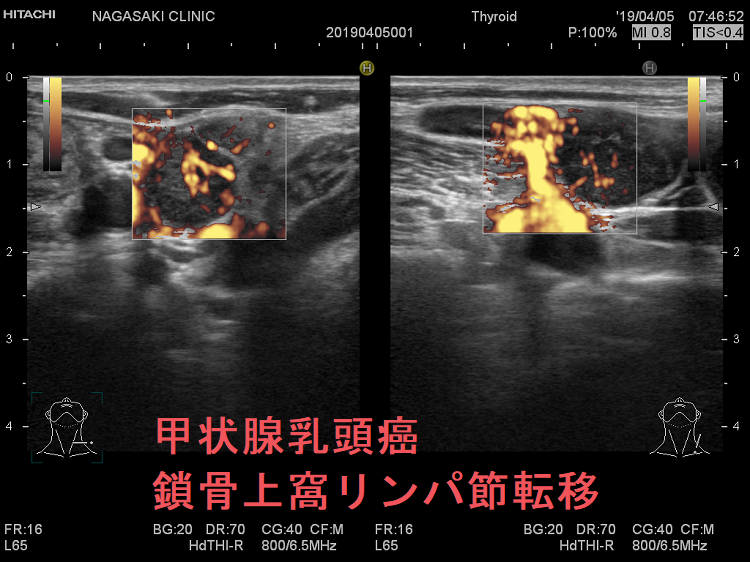

甲状腺乳頭癌 鎖骨上窩リンパ節転移 超音波(エコー)画像

甲状腺乳頭癌 左鎖骨上窩リンパ節転移 超音波(エコー)画像;いびつな形で、周囲との境界が一部不明瞭化して浸潤が疑われる。リンパ門は消失し、砂粒状石灰化が著明

甲状腺乳頭癌 鎖骨上窩リンパ節転移 超音波(エコー)画像 ドプラーモード

甲状腺乳頭癌 左鎖骨上窩リンパ節転移 超音波(エコー)画像 ドプラーモード;内部に異常な走行の血管を認め、血流豊富。

ケース④

甲状腺乳頭癌 鎖骨上窩リンパ節転移 超音波(エコー)画像 ドプラーモード2

甲状腺乳頭癌 左鎖骨上窩リンパ節転移 超音波(エコー)画像 ドプラーモード;いびつな形のリンパ節内部に異常な走行の血管を認め、血流豊富。